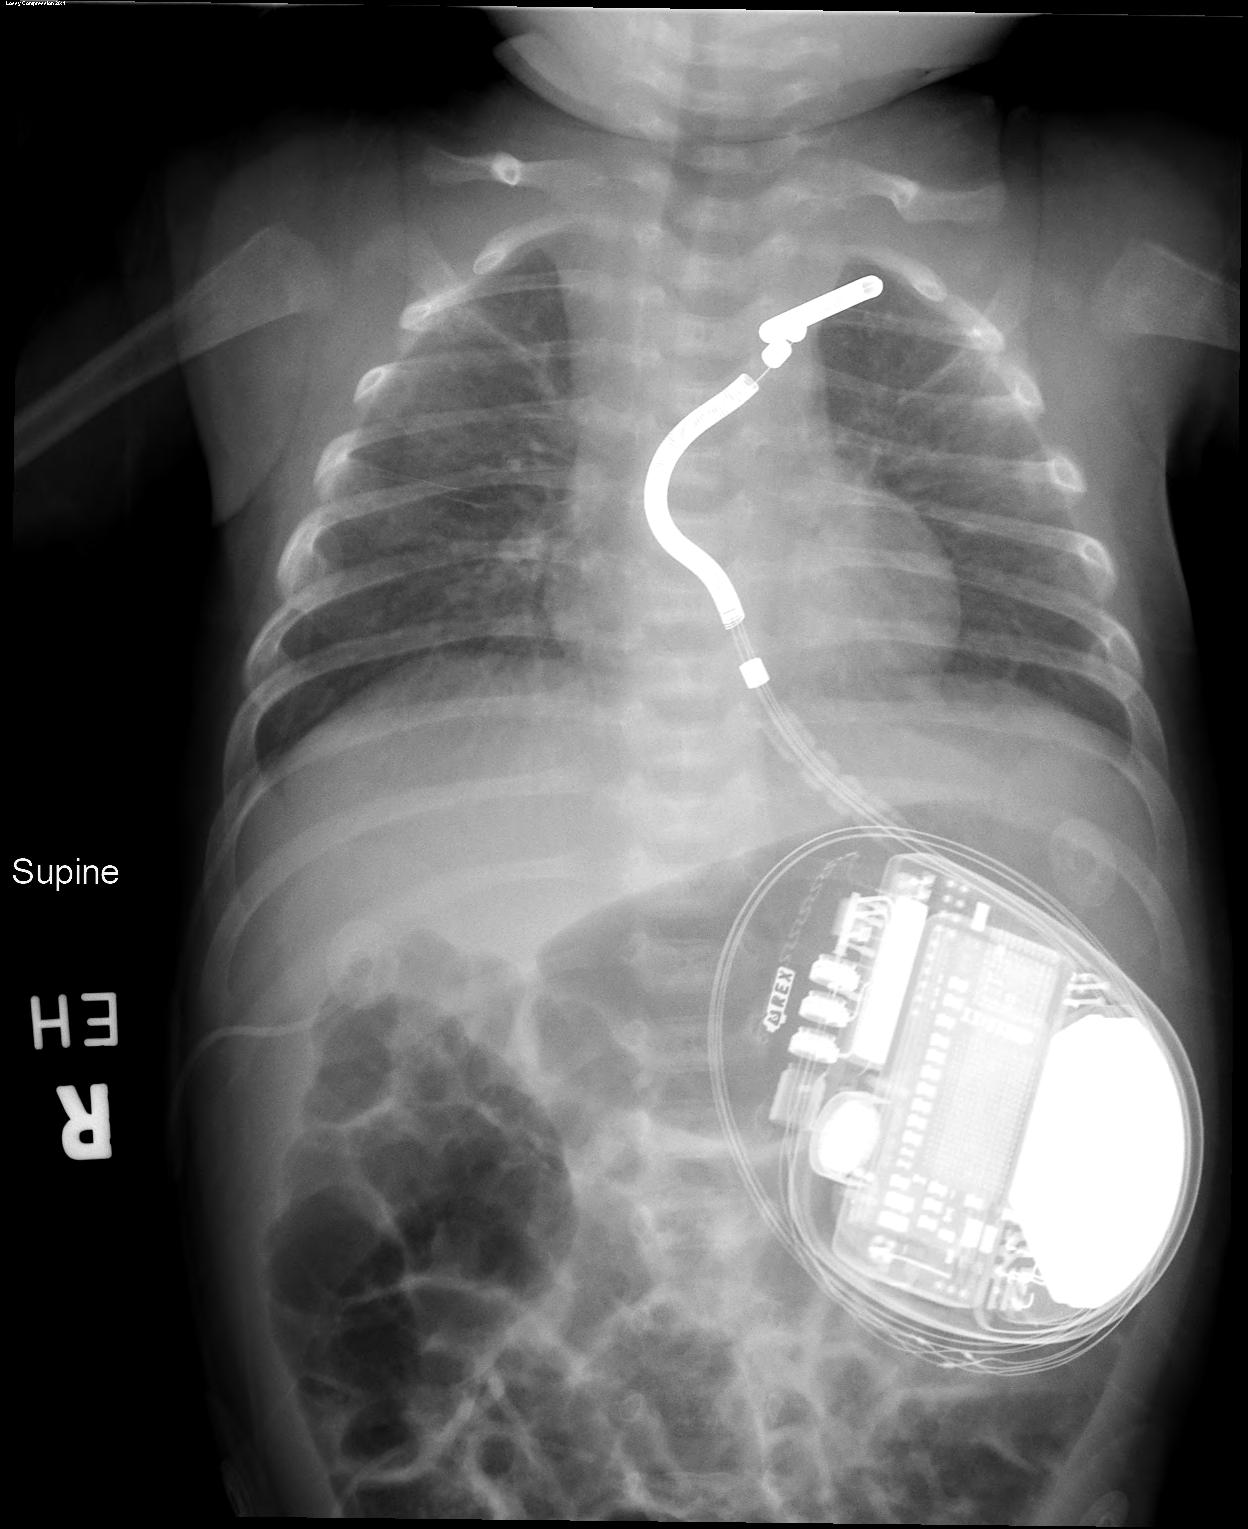

The device and battery were placed in Fletcher’s abdomen below the rib cage, with the single, critical lead wire snaking vertically just below his breastbone to sit just in front of the heart but not directly attached to the heart tissue.

While Fletcher remained under close watch in the hospital’s cardiac ICU, Sassan Hashemi, MD, another member of Division of Pediatric Cardiothoracic Surgery at Cincinnati Children’s, performed a critical task. Using imaging data from Fletcher’s chest CT scan, Hashemi constructed a 3D model of Fletcher’s heart and chest cavity. The process took less than a day.

The 3D results mattered because if the surgical planning had considered only a flat 2D plane, there would not have been enough room to fit a critical 9-cm portion of the device’s lead. But by curving the wire in both vertical and horizontal ways there was just enough room, Connor says.

“This procedure would not have been possible without the 3D model,” Connor says. “It demonstrated that the lead could fit in the desired space and allowed for virtual trialing of multiple positions within the chest.”

Fletcher’s procedure was performed June 6, 2025. He was a month and a half old.